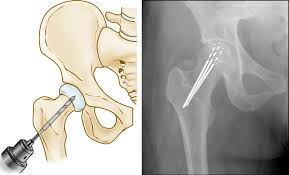

Minimally invasive and robotic-assisted surgery are key to quick recovery. Robotic technology allows highly accurate implant placement, ensuring optimal alignment and joint stability. Minimally invasive procedures reduce incision size, minimize tissue damage, and shorten hospital stays.

These advanced methods enable patients to start gentle movements and physiotherapy exercises almost immediately after surgery. Faster rehabilitation, reduced pain, and improved functional outcomes make these techniques ideal for patients seeking rapid recovery while maintaining long-term joint health.

Each patient receives a customized surgical plan based on imaging, clinical evaluation, and functional assessment. Advanced methods such as robotic-assisted and minimally invasive procedures help restore joint alignment, relieve pain, improve mobility, and minimize post-operative complications. Patients experience faster rehabilitation and regain independence safely.